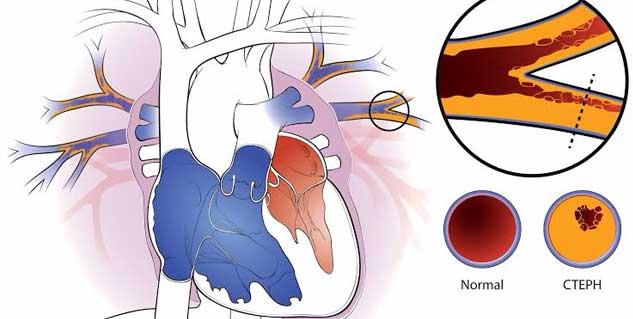

The Chronic Thromboembolic Pulmonary Hypertension (CTEPH) Market is undergoing rapid evolution driven by novel therapies, expanding clinical evidence and refined disease management protocols. As industry players intensify R&D and adopt digital health tools, business growth is reshaping competitive dynamics and unlocking new market opportunities.

Market Size and Overview

The Global Chronic Thromboembolic Pulmonary Hypertension (CTEPH) Market size is estimated to be valued at USD 1.51 Bn in 2025 and is expected to reach USD 2.47 Bn by 2032, exhibiting a CAGR of 7.3% from 2025 to 2032.

Rapid pipeline expansions, particularly in soluble guanylate cyclase stimulators, are driving market growth, while reimbursement challenges and diagnostic delays remain notable market restraints. Recent industry analysis highlights that North America captures over 40% of market revenue, with Asia Pacific emerging as the fastest-growing region in terms of market share. This market report underscores shifting market dynamics and evolving market trends.

• Major academic centers in Germany deployed balloon pulmonary angioplasty in 2024, reducing mean pulmonary arterial pressure by 25% and demonstrating significant long-term quality-of-life gains—an example of targeted clinical integration and market growth strategies.

• In mid-2025, a U.S. specialty hospital integrated telemonitoring for post-surgical CTEPH patients, cutting readmission rates by 18% and showcasing digital health’s role in driving market opportunities within specialized care segments.

• A Japan-based consortium utilized combination therapy (riociguat plus macitentan) in 2024 for inoperable CTEPH, recording a 30% improvement in exercise capacity and reinforcing market drivers around multimodal treatment approaches and refined patient stratification.

• In 2024, FDA granted expanded approval for macitentan in CTEPH, enhancing treatment access and stimulating market revenue growth.

• The European Medicines Agency fast-tracked a novel oral anticoagulant for CTEPH in 2025, reflecting regulatory support for innovation and business growth.